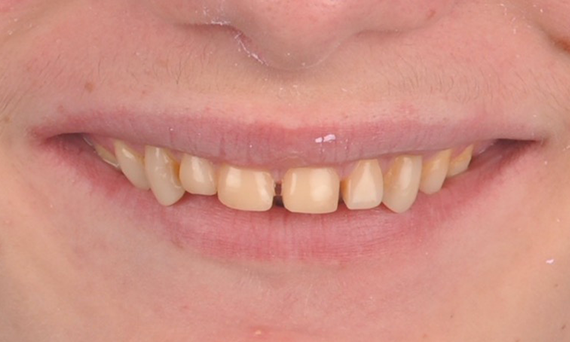

Avant : l’objectif du traitement était de réhabiliter le maxillaire antérieur et la mandibule pour une amélioration esthétique. Le diagnostic clinique a révélé une ameloenesis imperfecta.

Après : restauration fabriquée en laboratoire à partir de la céramique avancée au disilicate de lithium CEREC Tessera et, pour un résultat esthétique élevé, facettes en Celtra Ceram.